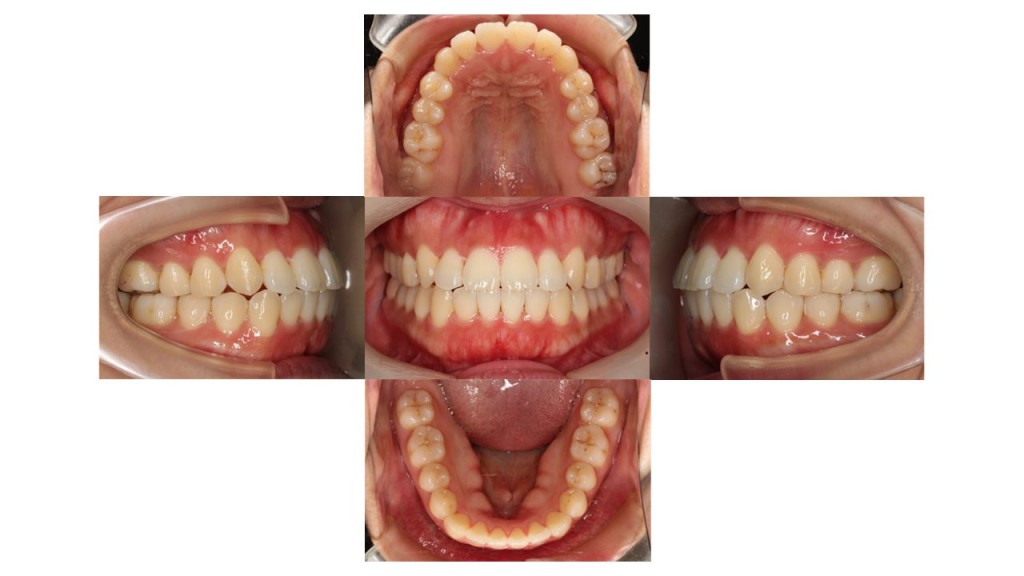

1年10ヵ月経過の口腔内の状態です。

八重歯・前歯の凸凹が改善したとご満足いただけました。